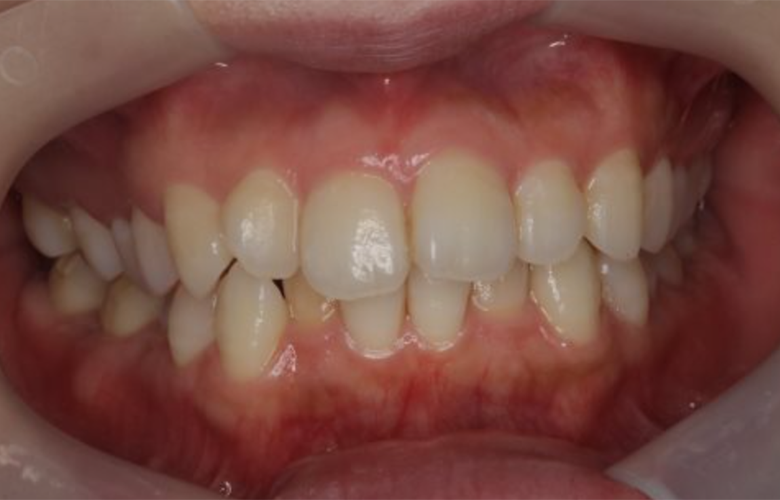

前歯のガタつきをマウスピース矯正で改善した症例(30代女性・非抜歯)

治療前 ![]() |

「前歯の重なりが気になり、人前で笑うのをためらってしまう。できるだけ目立たず短期間で整えたい」とのご相談で来院されました。 |

上下前歯部に軽度〜中等度の叢生(歯の重なり)を認めました。特に上顎前歯部にスペース不足があり、歯列の不調和が審美的な障害となっていました。咬合関係は大きな問題はなく、骨格的な異常も認められなかったため、非抜歯での矯正治療が可能と判断しました。 |